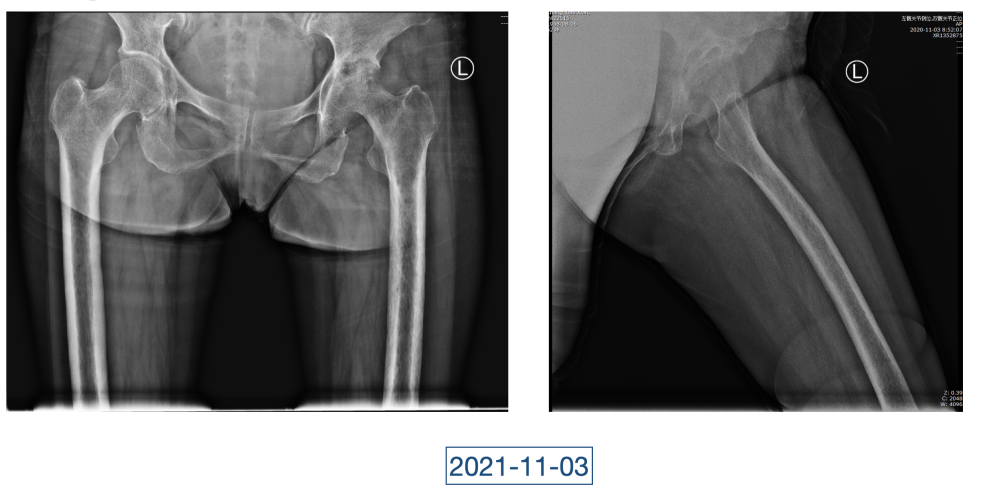

在黄大娘入院第四天,李辉将她推入检查室,结果很快出来了,为烟曲霉菌感染。这个结果验证了李辉的想法,也解释了此前抗感染药物为何一直不奏效。“找到元凶就好办了,对症用药就可以。真菌感染本来治疗时间就很长,骨科类感染灶治疗时间更长,用了5个月的时间,终于治好了。”

近日随访得知黄大娘身体好转,李辉脸上的笑容掩饰不住,他说,据查阅文献,11处感染灶,这是全世界感染灶最多的骨关节感染,但现在,这罕见、复杂的病已经被治愈。